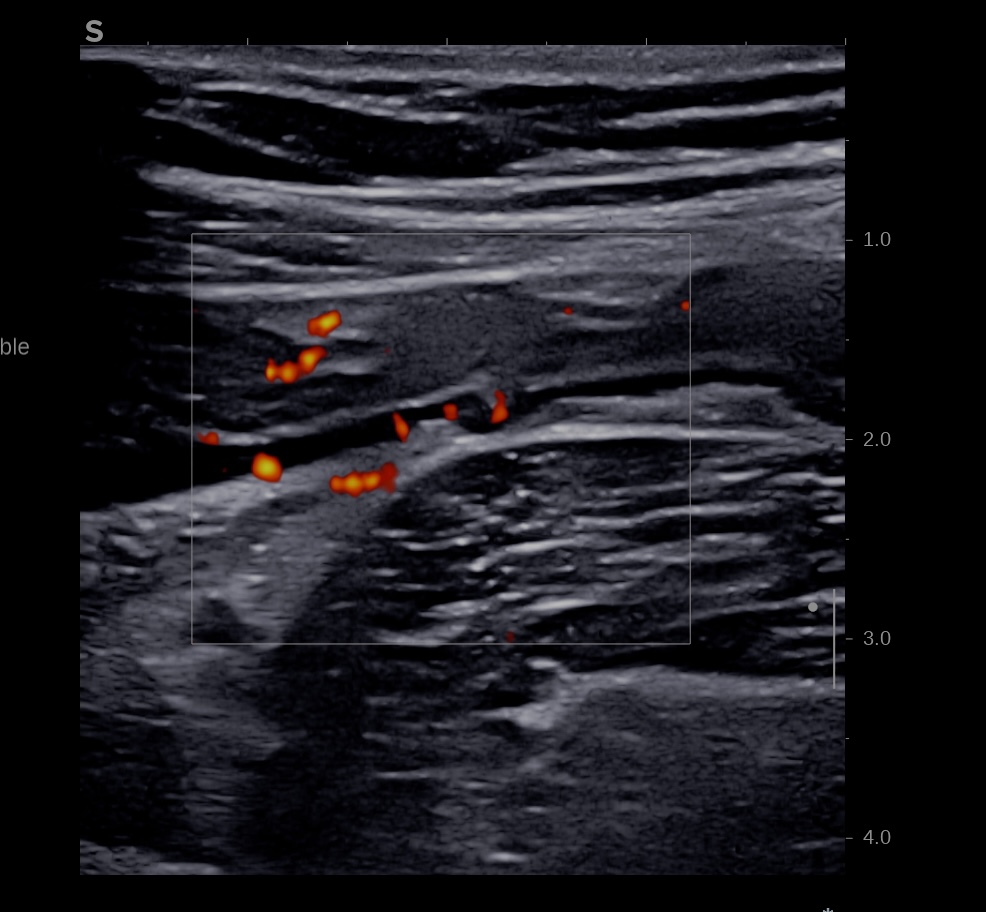

3. L’inflammation atteint la périphérie de l’anse donc

– hyperactivité doppler intense de la paroi et de la graisse (Limberg 3)

Epaississement considérable par endroit (10 ou 11 mm), disparition totale de la structure en couches, déformation de la surface avec ulcérations, déformation des contours, infiltration de la graisse, hyperactivité Doppler

Le Score de Milan (MUC) est à 17.4

Les images échographiques correspondent parfaitement aux images endoscopiques, et sont finalement beaucoup plus précises que les images scanographiques.